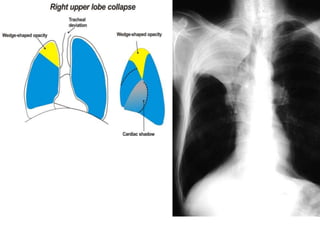

Radiologic signs of collapse

The term collapse is used when a whole lobe or lung is involved.

Atelectesis is defined as diminished volume

affecting all or part of a lung, whichmay or may

not include loss of normal lucency in the affected

part of lung .

Pulmonary atelectasis can be divided into six

types, based on mechanism: resorptive, adhesive,

compressive, passive, cicatrization, and gravity-

dependent

LOBAR ATELECTASIS

Radiologic signs of lobar atelectasis :- Direct

or Indirect .

Direct signs include increased opacification

of the airless lobe and displacement of

fissures.

Indirect signs include displacement of hilar and

cardiomediastinal structures toward the side of

collapse, narrowing of the ipsilateral intercostal

spaces, elevation of the ipsilateral

hemidiaphragm, compensatory hyperinflation

and hyperlucency of the remaining aerated

lung, and obscuration or desilhouetting of the

structures adjacent to the collapsed lung

(eg, diaphragm and heart borders). Additional

radiologic features vary according to the site of

atelectasis.